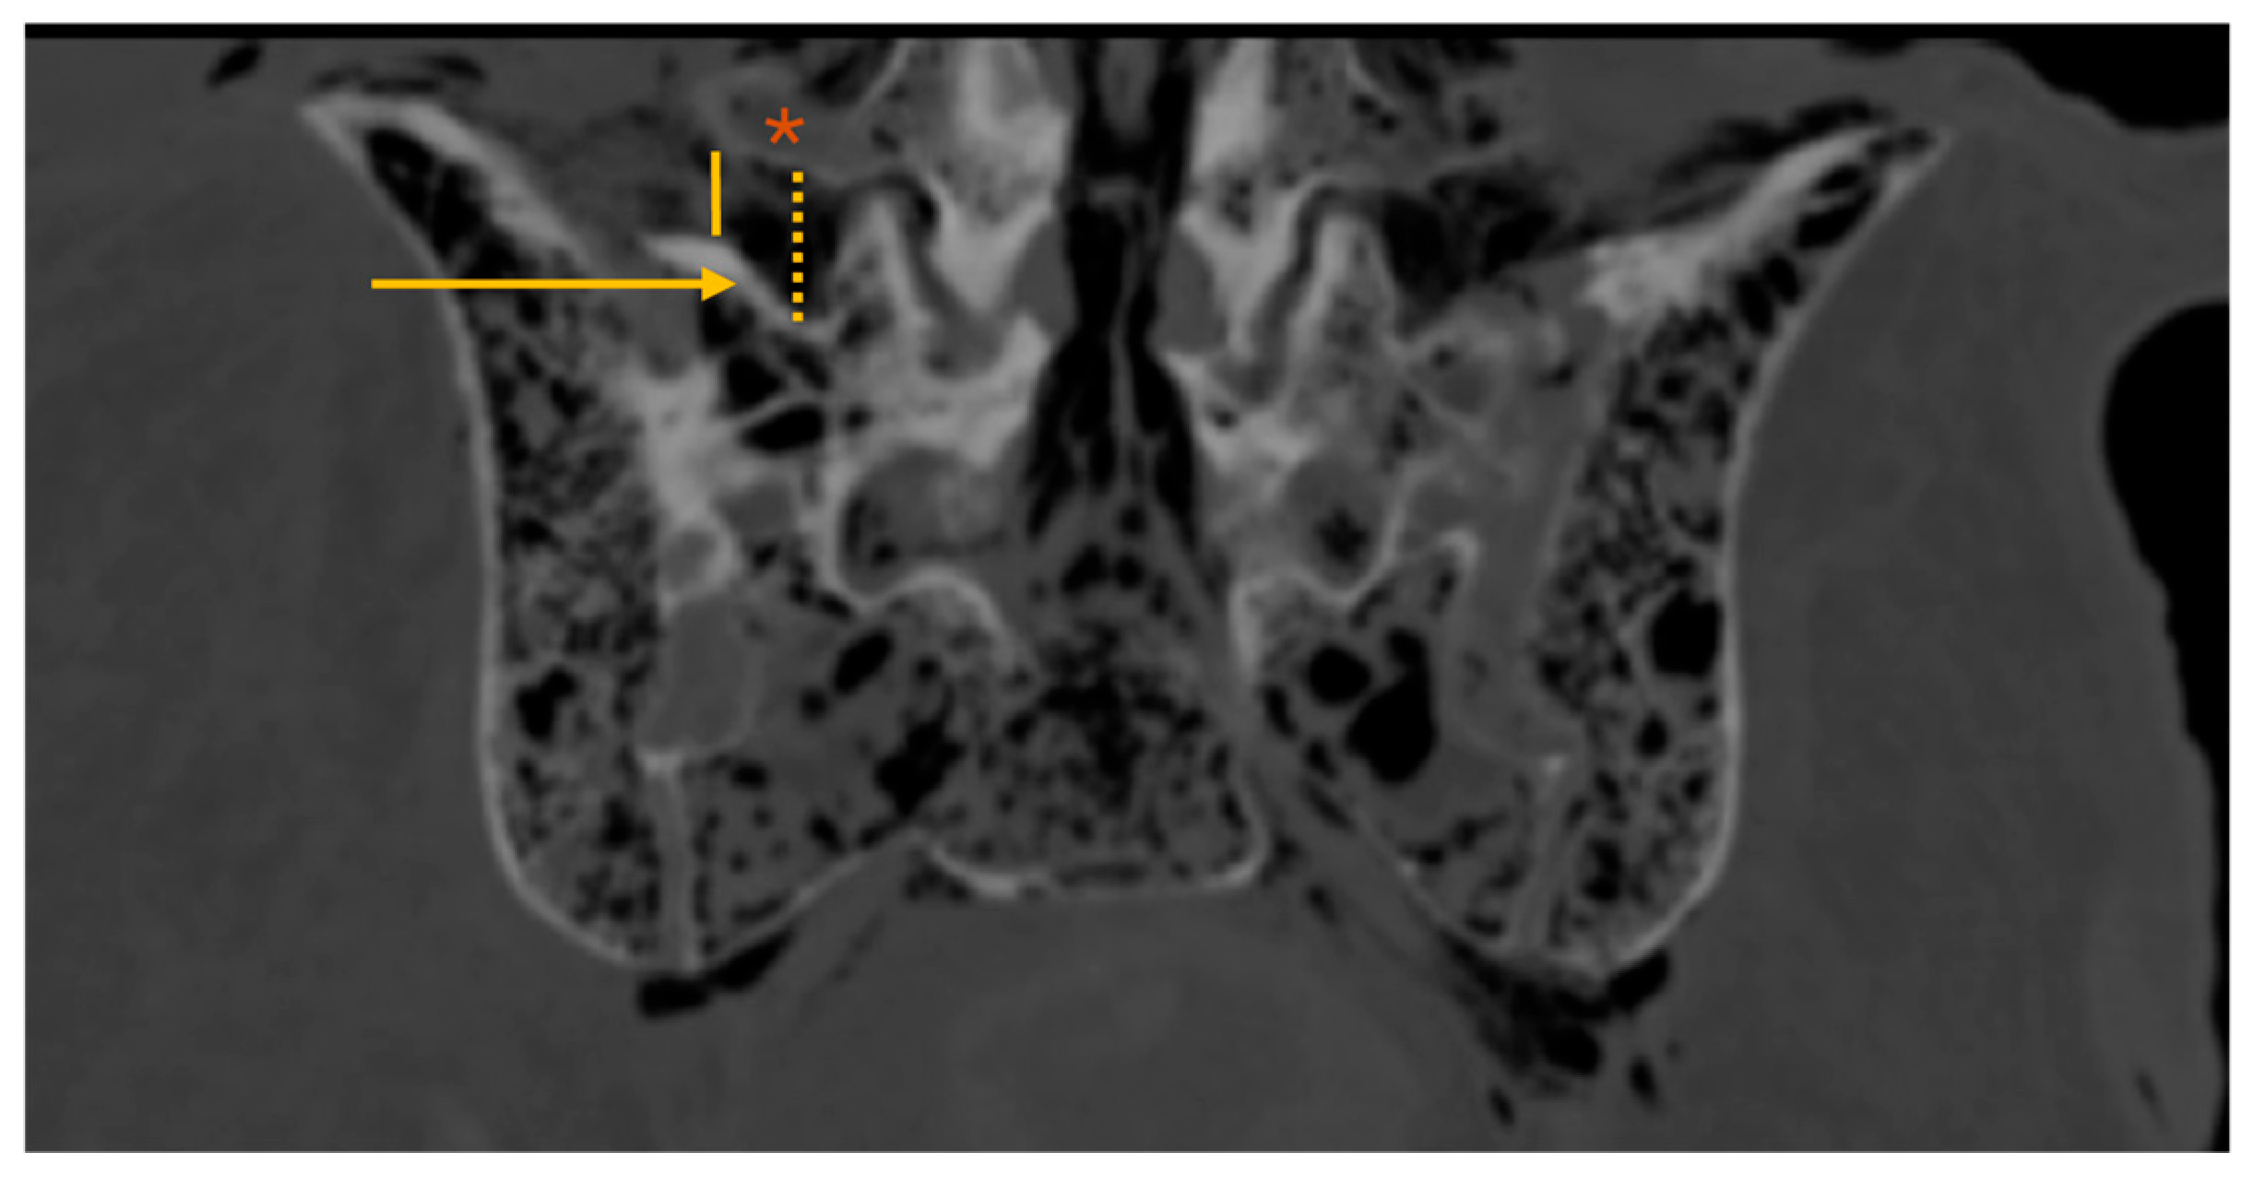

• MaxTP-sacrum and minTP-sacrum: maximum and minimum distance from the inferior border of the L5 TP to the superior border of the sacral ala, respectively, (coronal plane intersecting the L5 TP center; Figure 3)

The maxTP-sacrum distance (Figure 3) was 11.1(4.0)mm, consistently located in the second quarter of the L5 TP (from its base). The mean minTP-sacrum distance (Figure 3) was 5.6±2.9mm, always near the L5 TP tip. No statistically significant differences were observed between nondysmorphic and dysmorphic upper sacral morphology (p=0.662 and p=0.498, respectively).

Figure 3. Lumbar spine CT – coronal plane; *: L5 transverse process; arrow: sacral ala; dotted yellow line: maxTP-sacrum (maximum distance from the inferior border of the L5 transverse process to the superior border of the sacral ala); solid yellow line: minTP-sacrum (minimum distance from the inferior border of the L5 transverse process to the superior border of the sacral ala).